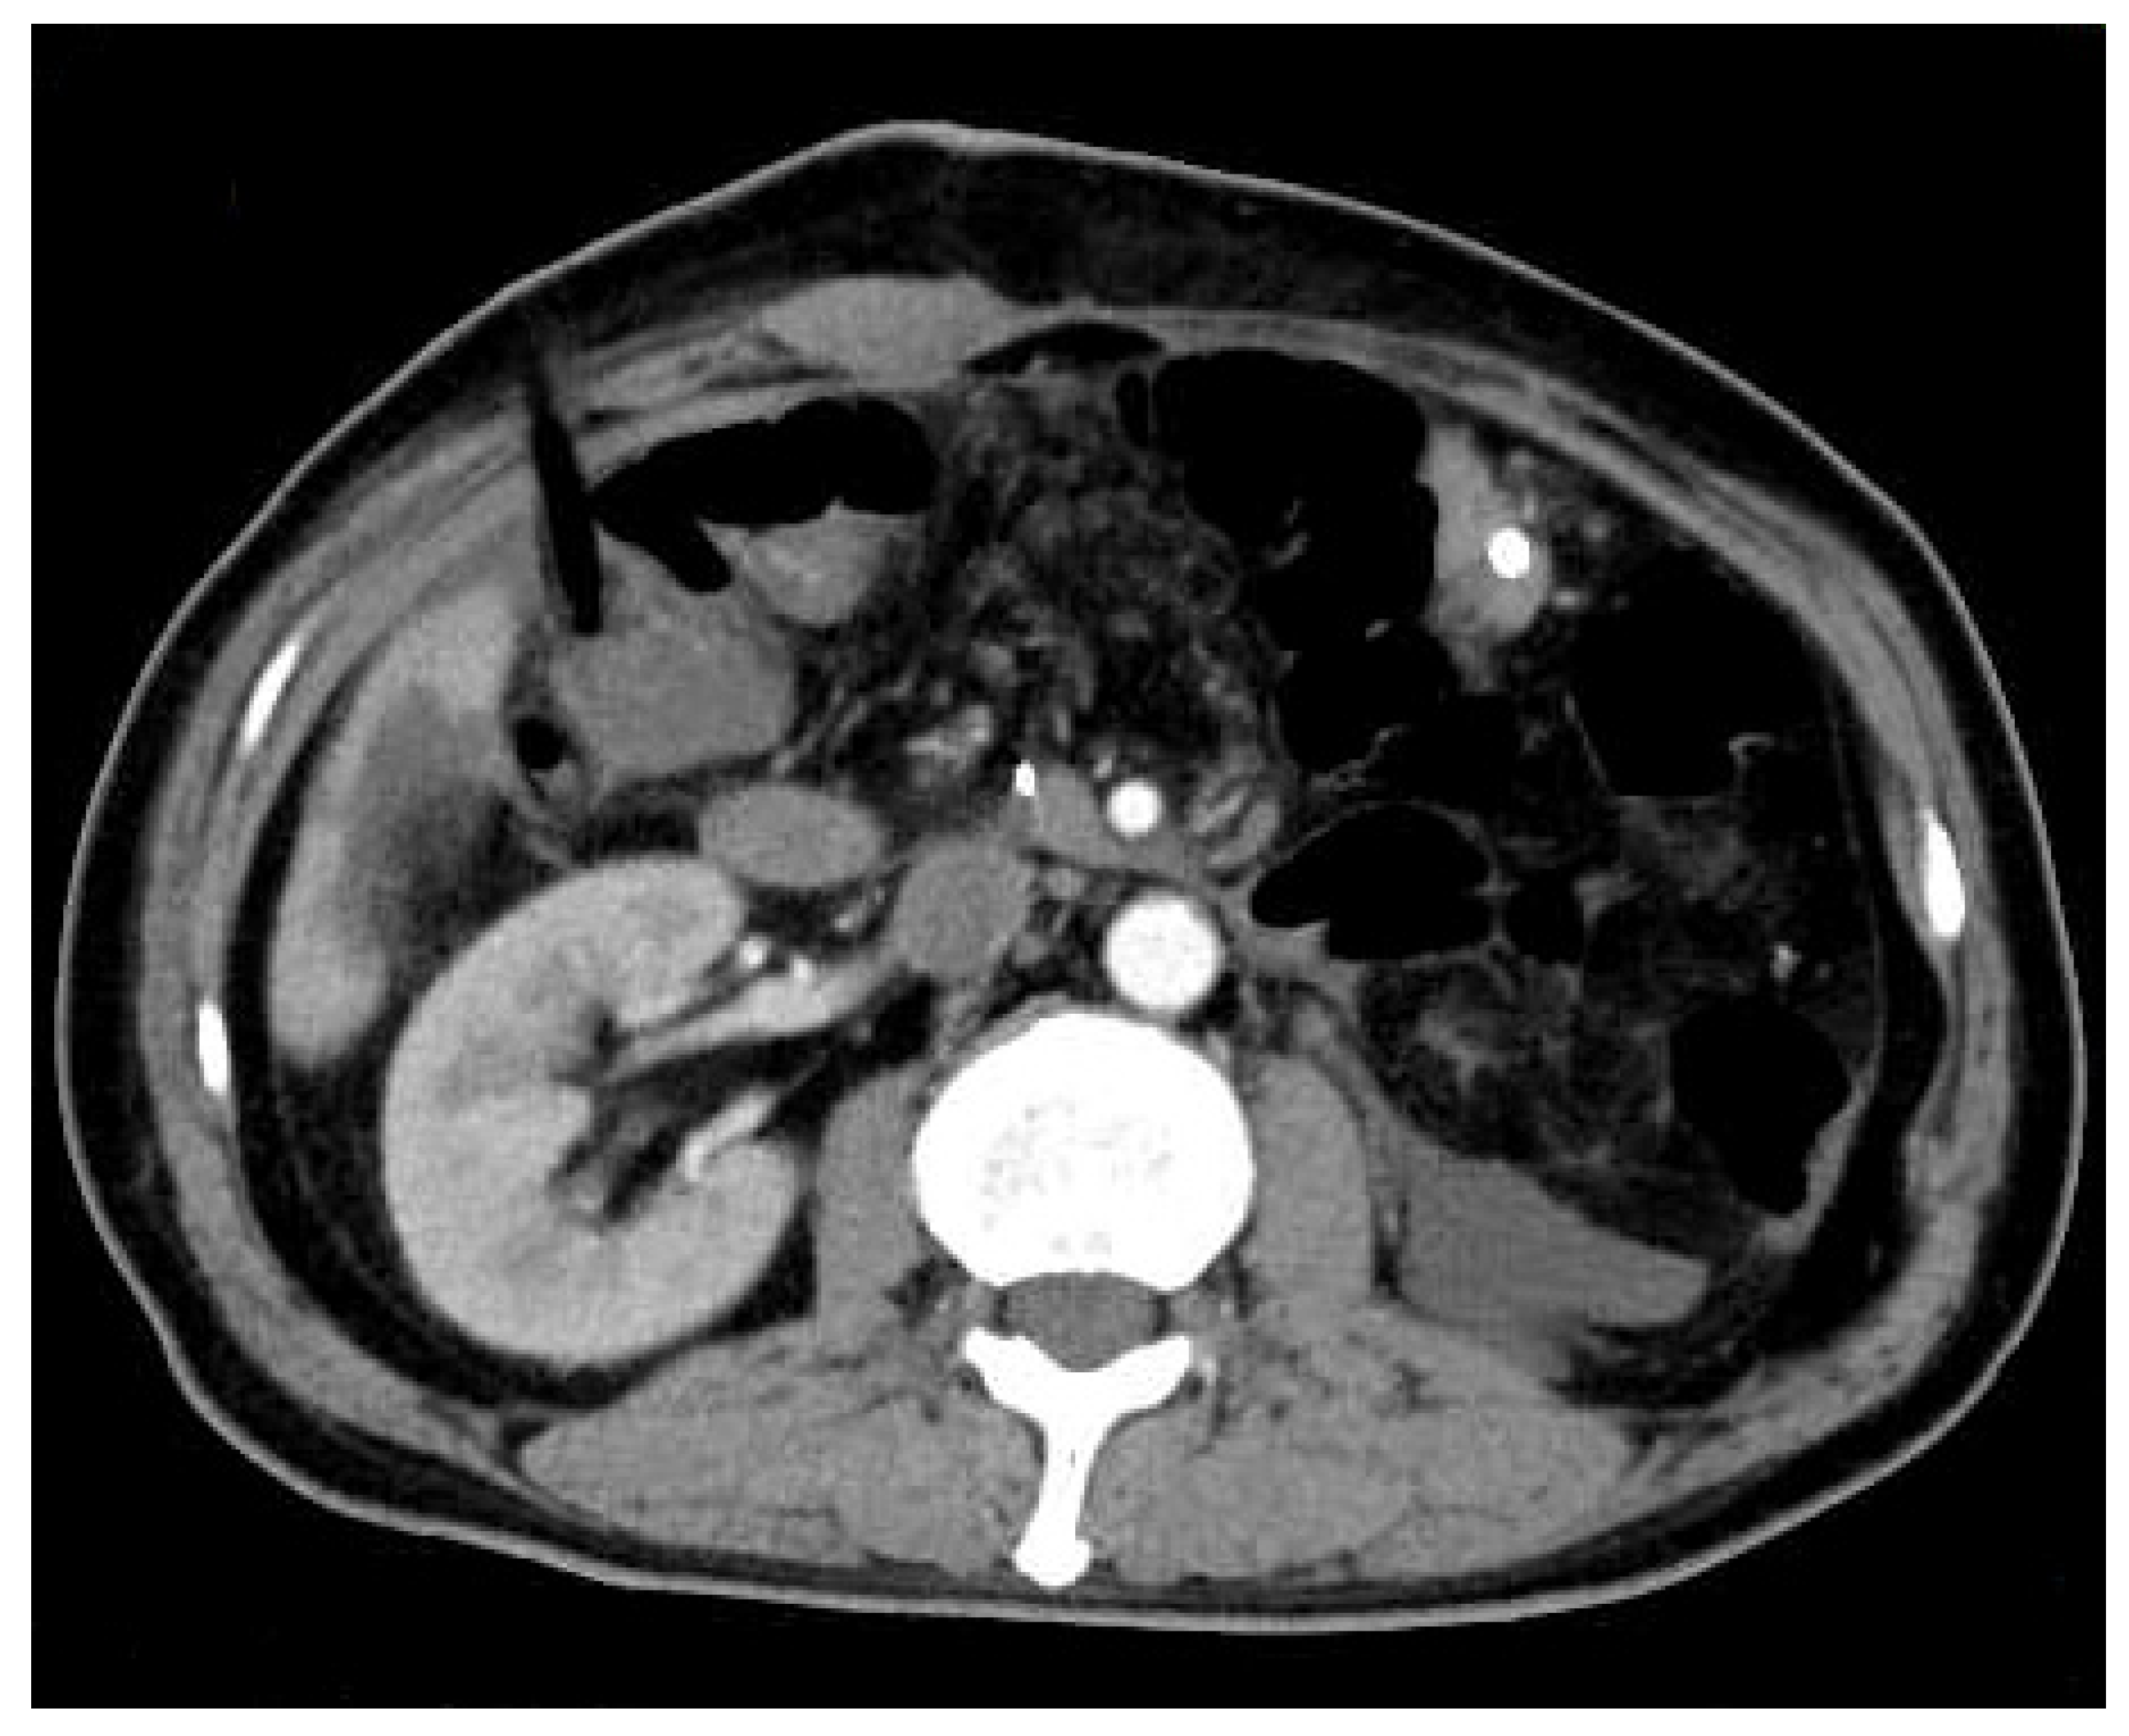

Clear Cell Renal Cell Carcinoma Metastasized to the Ampulla of Vater 16 Years after Nephrectomy—A Rare Case